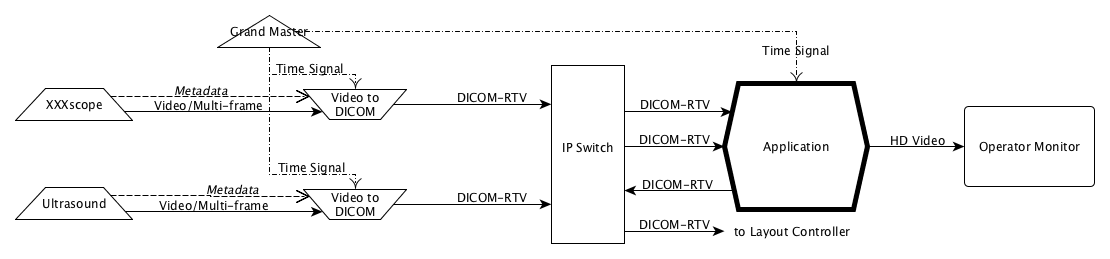

- PPPP.7. Example of DICOM Real-Time Video Implementation

- PPPP.8. Storage Considerationa

- PPPP.9. Example of Engineering Implementation